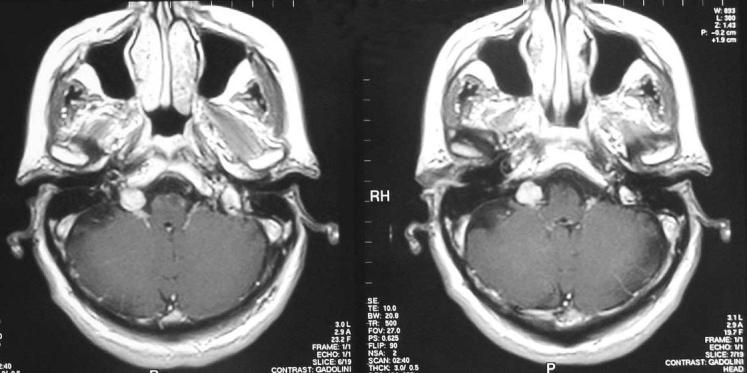

An unusual case presenting with hypertensive crisis.